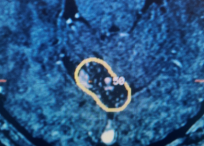

- Brain Tumors

- Brain Metastases

- Gliomas